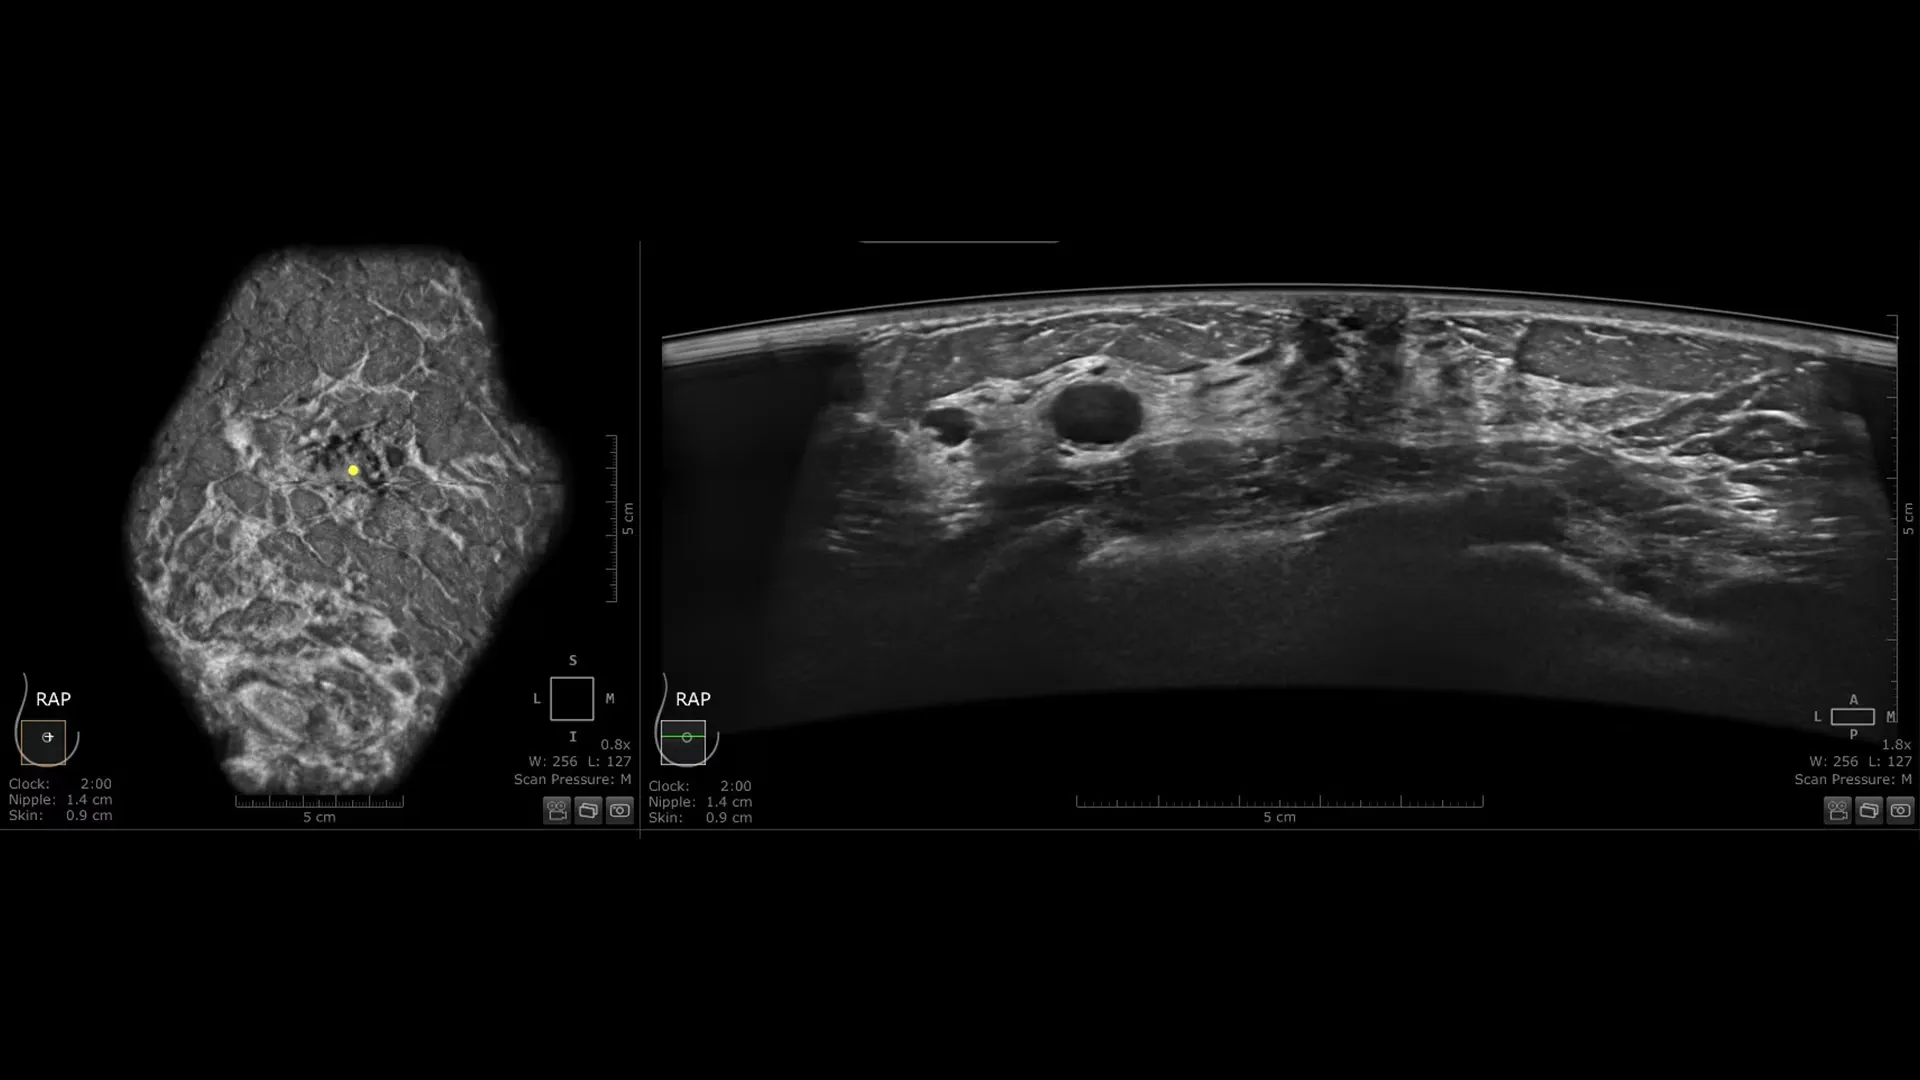

Invenia ABUS Premium osmišljen je za visoku propusnost pacijentica i iznimnu kvalitetu prikaza, pružajući visoku razinu dijagnostičke sigurnosti. Zahvaljujući inovativnom dizajnu, sustav je jednostavan za korištenje, reproducibilan, neovisan o korisniku, standardiziran te omogućuje očitanje nalaza s bilo koje lokacije.

Nova Reverse Curve™ sonda za poboljšane performanse

Njezin blago zakrivljen oblik duljine 15,3 cm prati prirodnu konturu dojke, povećavajući udobnost pacijentice* i osiguravajući potpuni kontakt za sveobuhvatnu pokrivenost. Unaprijeđena kvaliteta prikaza* dodatno povećava dijagnostičku sigurnost pri očitanju ABUS pregleda.

- cSound Imageformer, softverska obrada slike, omogućuje iznimno precizan i ponovljiv prikaz zahvaljujući automatskom fokusiranju u svakoj točki slike

- Do 93%⁵ osjetljivosti u detekciji lezija te smanjenje vremena očitanja za 33% uz QVCAD™⁶

- Smanjenje broja benignih biopsija do 55% uz Koios DS™ Breast⁷